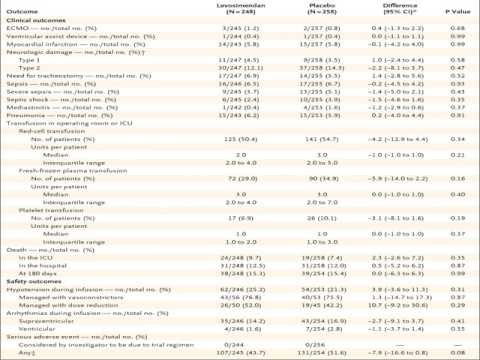

Levosimendan como soporte hemodinámico post cirugía cardíaca. Dr. Guido Vannoni. Residencia de Cardiología. Hospital C. Argerich. Buenos Aires